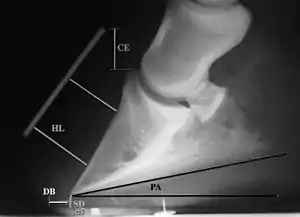

Radiographs

Radiographs are an important part of evaluating the laminitic horse. They not only allow the practitioner to determine the severity of the episode, which does not always correlate with degree of pain,[1] but also to gauge improvement and response to treatment. Several measurements are made to predict severity. Additionally, radiographs also allow the visualization and evaluation of the hoof capsule, and can help detect the presence of a lamellar wedge or seromas.[1] The lateral view provides the majority of the information regarding degree of rotation, sole depth, dorsal hoof wall thickness, and vertical deviation.[1][17] A 65-degree dorsopalmar view is useful in the case of chronic laminitis to evaluate the rim of the coffin bone for pathology.[1]

Several radiographic measurements, made on the lateral view, allow for objective evaluation of the episode.

- Coronary extensor distance (CE): the vertical distance from the level of the proximal coronary band to the extensor process of P3. It is often used to compare progression of the disease over time, rather than as a stand-alone value. A rapidly increasing CE value can indicate distal displacement (sinking) of the coffin bone, while a more gradual increase in CE can occur with foot collapse. Normal values range from 0–30 mm, with most horses >12–15 mm.[1]

- Sole depth (SD): the distance from the tip of P3 to the ground.

- Digital breakover (DB): distance from the tip of P3 to the breakover of the hoof (dorsal toe).[1]

- Palmar angle (PA): the angle between a line perpendicular to the ground, and a line at the angle of the palmar surface of P3.

- Horn:lamellar distance (HL): the measurement from the most superficial aspect of the dorsal hoof wall to the face of P3. 2 distances are compared: a proximal measurement made just distal to the extensor process of P3, and a distal measurement made toward the tip of P3. These two values should be similar. In cases of rotation, the distal measurement will be higher than the proximal. In cases of distal displacement, both values will increase, but may remain equal. Therefore, it is ideal to have baseline radiographs for horses, especially for those at high-risk for laminitis, to compare to should laminitis ever be suspected. Normal HL values vary by breed and age:[1]